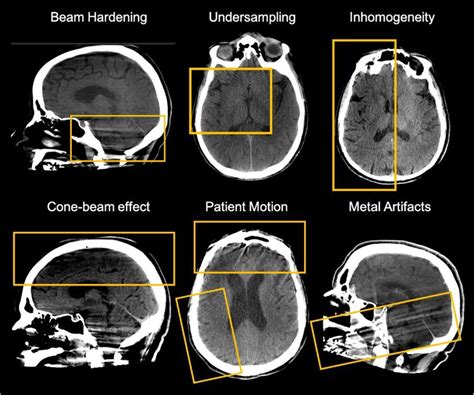

For instance, in image processing, artefacts can appear as noise or distortions in the image. These can be caused by various factors, such as compression, transmission errors, or sensor noise. Techniques like filtering and denoising are used to reduce these artefacts and improve image quality.